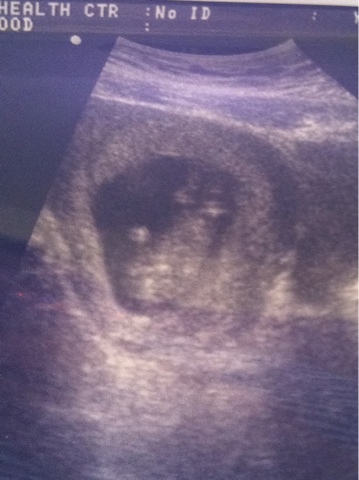

March 2 Ultrasound

Baby R was just chillin out today! Upside down, ankles crossed and hands behind the head...I've been spoiled by Shady Grove's ultrasound machine. These are so blurry! But, the baby is upside down, so, that's what you're seeing!